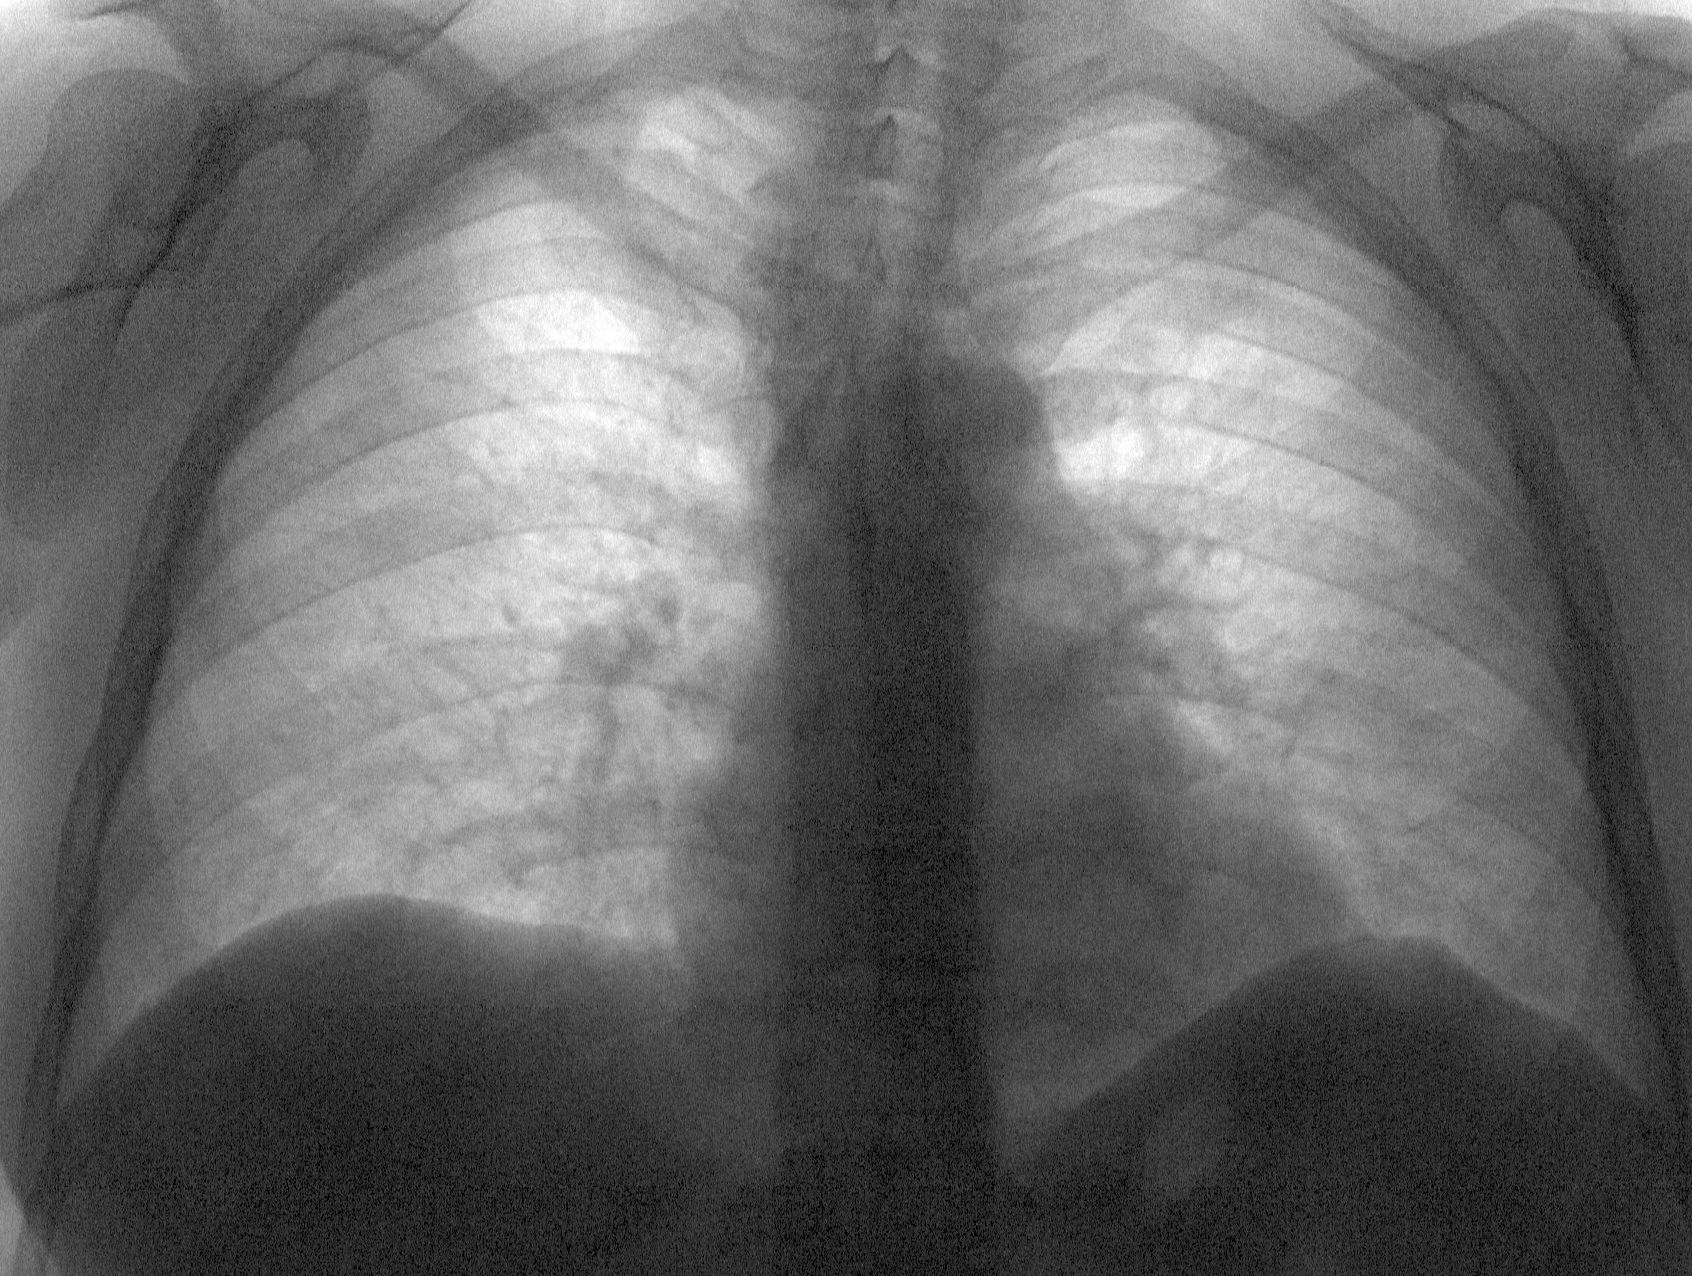

Ну и очередное динамическое наблюдение. На 1-м снимке еще думал, может какой-либо застой?, но написал таки двустороннюю пневмонию ( не поняли бы). А сегодня пациент в отличном здравии пришел на контроль.

А сегодня пациент в отличном здравии пришел на контроль.

В отличном здравии, а р-динамика отрицательная...

Коллеги, можно допустить, что это связано с " ножницами" между клинической и рентгенологической картиной, рентгенологическая картина всегда отстаёт от клинической, запаздывает, т.е. пациент чувастует себя значительно лучше, а по снимками патология сохраняется или явное ухудшение в сравнении с первым снимком( ведь какое- то время шло прогрессирование рентгенкартины изменений в лёгких, даже на фоне лечения).